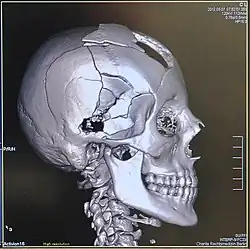

Head

CT scanning of the head is typically used to detect infarction (stroke), tumors, calcifications, haemorrhage, and bone trauma.[32] Of the above, hypodense (dark) structures can indicate edema and infarction, hyperdense (bright) structures indicate calcifications and haemorrhage and bone trauma can be seen as disjunction in bone windows. Tumors can be detected by the swelling and anatomical distortion they cause, or by surrounding edema. CT scanning of the head is also used in CT-guided stereotactic surgery and radiosurgery for treatment of intracranial tumors, arteriovenous malformations, and other surgically treatable conditions using a device known as the N-localizer.[33][34][35][36][37][38]

Volume rendering

A threshold value of radiodensity is set by the operator (e.g., a level that corresponds to bone). With the help of edge detection image processing algorithms a 3D model can be constructed from the initial data and displayed on screen. Various thresholds can be used to get multiple models, each anatomical component such as muscle, bone and cartilage can be differentiated on the basis of different colours given to them. However, this mode of operation cannot show interior structures.[117]

Surface rendering is limited technique as it displays only the surfaces that meet a particular threshold density, and which are towards the viewer. However, In volume rendering, transparency, colours and shading are used which makes it easy to present a volume in a single image. For example, Pelvic bones could be displayed as semi-transparent, so that, even viewing at an oblique angle one part of the image does not hide another.[118]